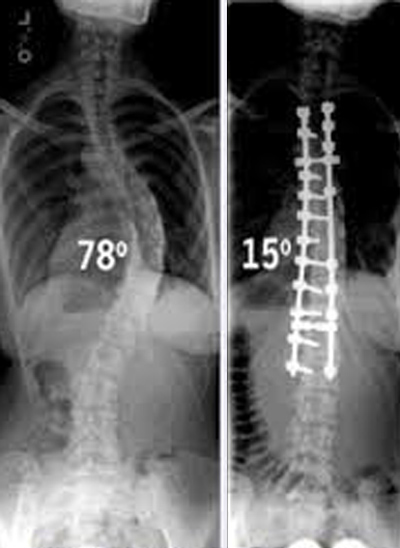

Στις μεγάλες σκολιωτικές γωνίες (πάνω από 45⁰) χρειάζεται εγχείρηση (σπονδυλοδεσία) που σήμερα είναι σχετικά εύκολη και αντιμετωπίζει καίρια το πρόβλημα, ώστε το σώμα ν΄ αποκτά φυσιολογική εμφάνιση.